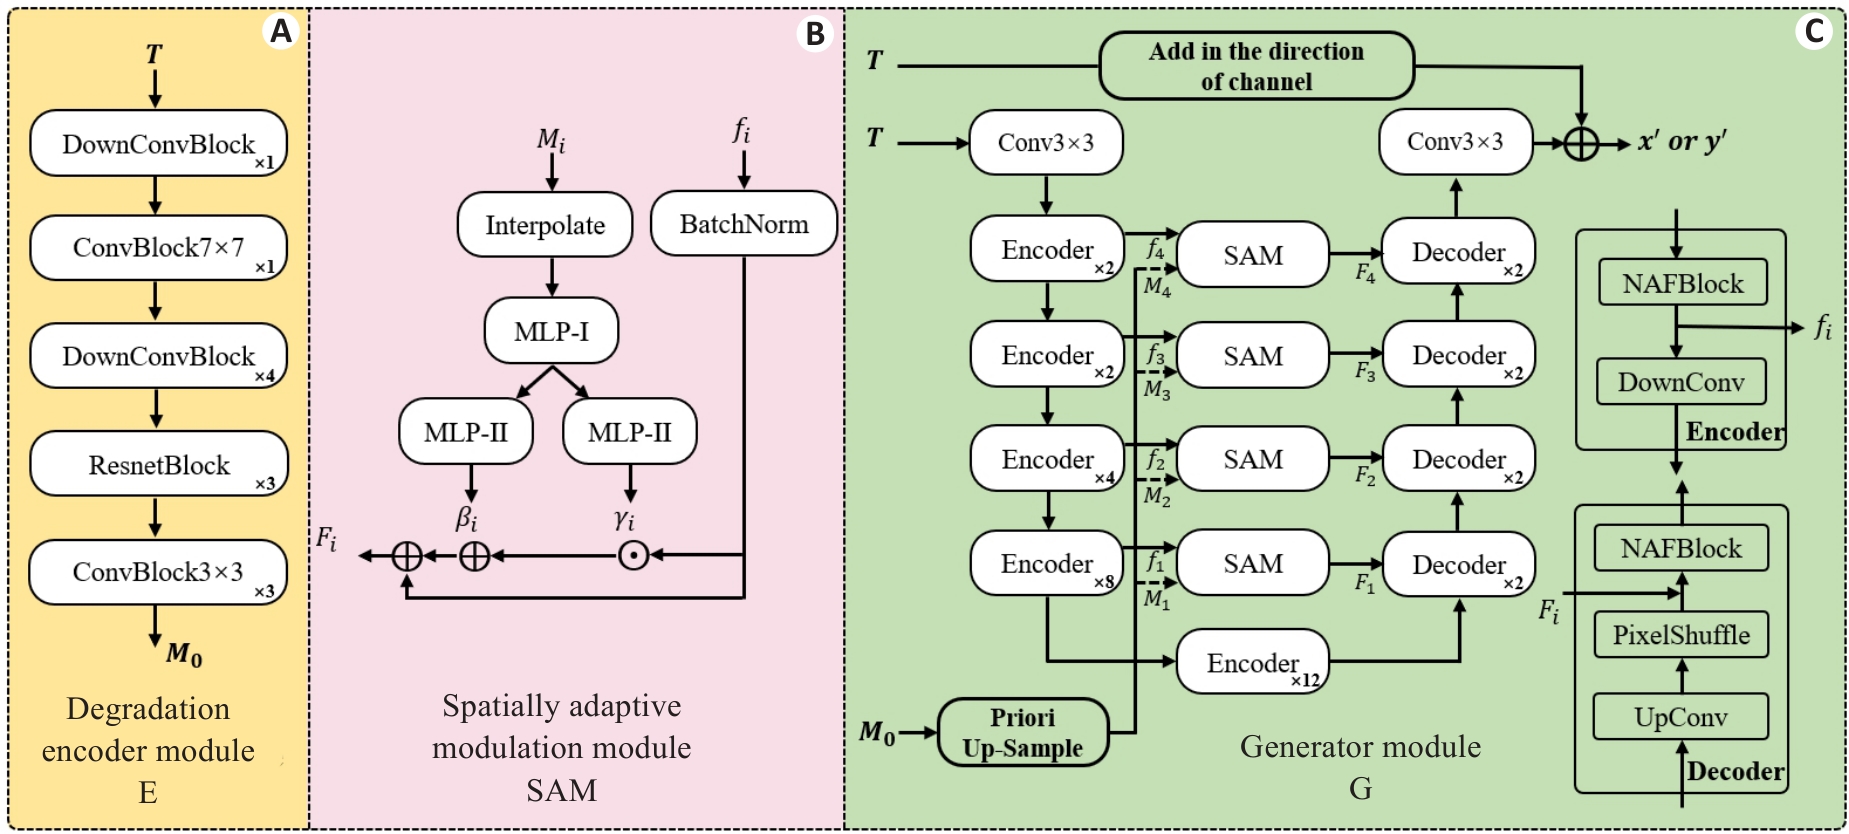

Fig.3 Detailed archetecture of the key modules. A: Degradation Encoder Module (E). B: Spatial Adaptive Modulation Module (SAM). C: Generator Module (G). The number of stacks for each smaller module is indicated at the bottom right corner.